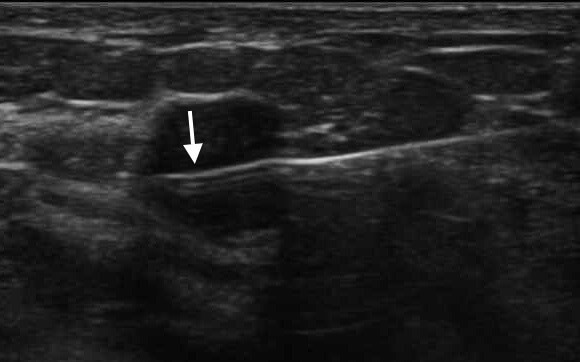

Ultrasound Guided Biopsies